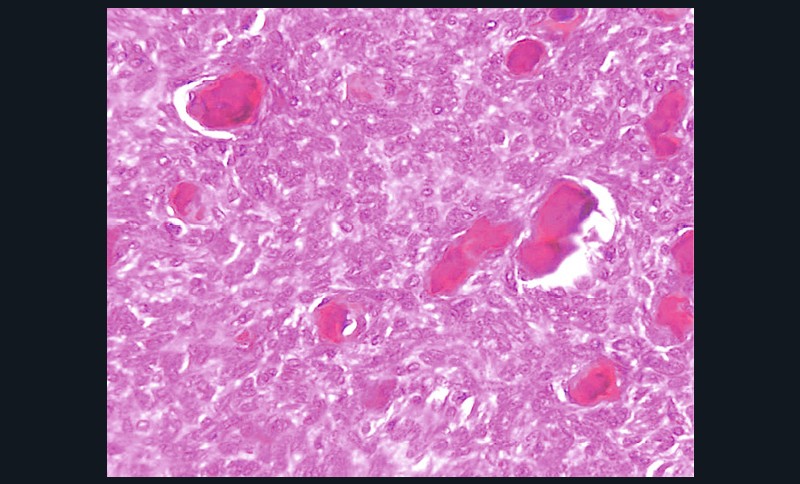

- Histologie : tissu conjonctif richement vascularisé + infiltrat massif de plasmocytes (fig. 1c).